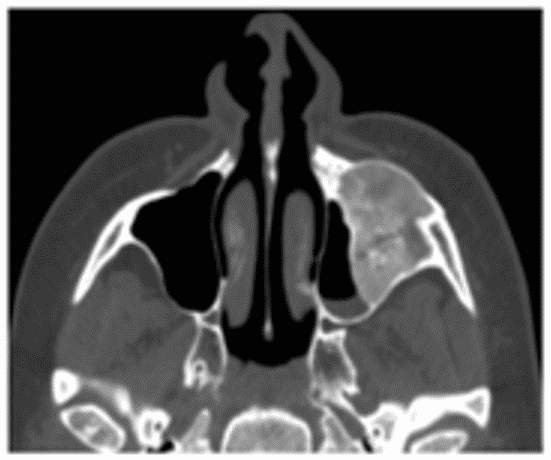

Фиброзная дисплазия на КТ характеризуется наличием относительно однородной, напоминающей матовое стекло, ткани плотностью, примерно, от 300 до 450 ед. Н, что ниже обычных денситометрических значений для спонгиозного слоя кости и соответствует плотности фиброзной ткани (рисунок 5).

Рис. 5. КТ околоносовых пазух, аксиальная плоскость. Фиброзная дисплазия верхнечелюстной (А), лобной (Б) пазух